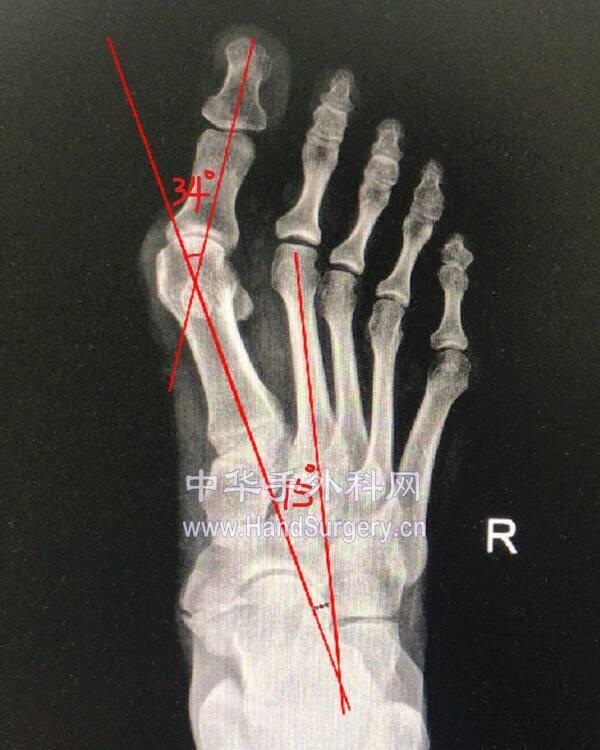

微信图片编辑_20191218175444.jpg 微信图片编辑_20191218175548.jpg

微信图片编辑_20191218175511.jpg 微信图片编辑_20191218175530.jpg

微信图片编辑_20191218175444.jpg 两侧均为中度

微信图片编辑_20191218175511.jpg